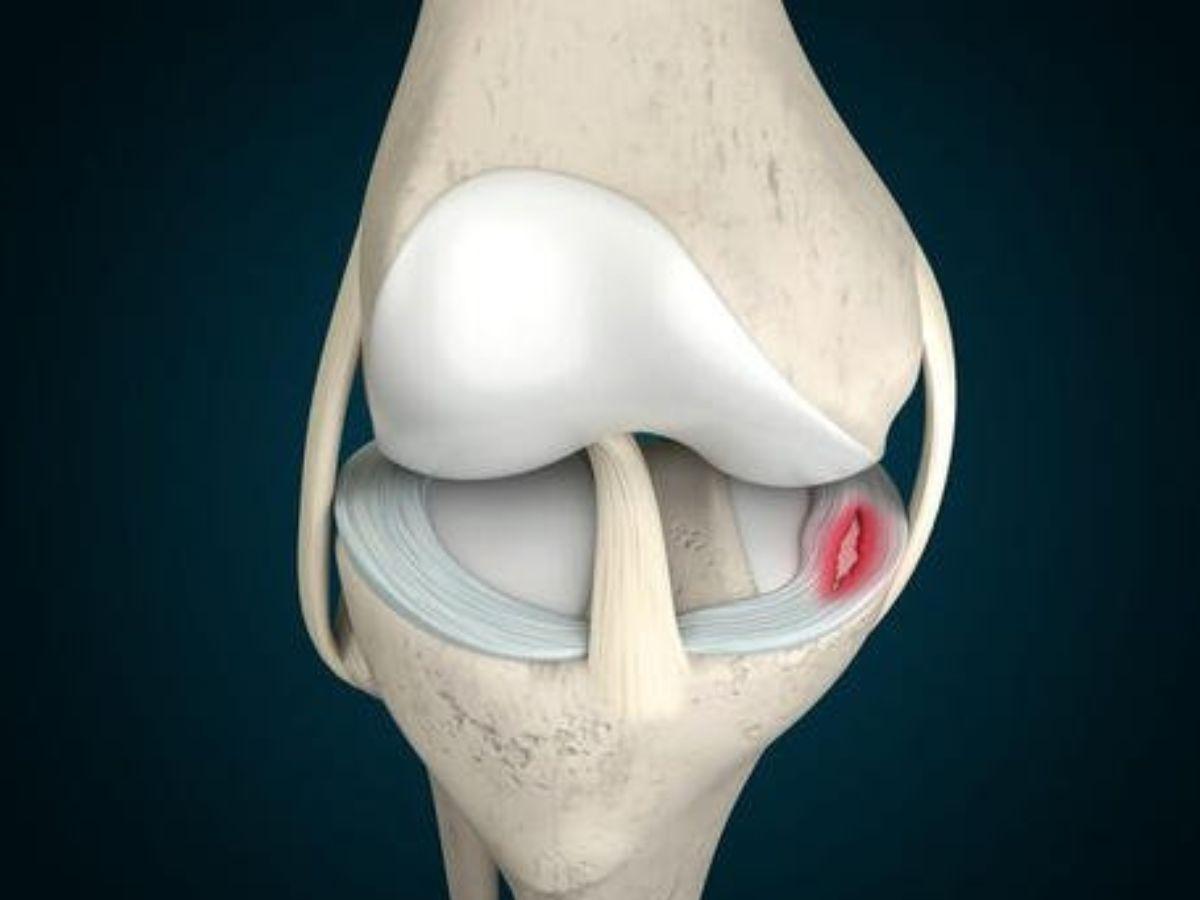

Rách sụn chêm (Meniscus tear)

Sụn chêm là bộ phận có tác dụng hấp thu lực tác động và ổn định hoạt động khớp gối. Nếu phần đầu gối bị xoắn hoặc tác động lực quá mạnh như chấn thương đầu gối khi ngã xe, chấn thương chân khi đá bóng có thể gây rách sụn chêm, gây cảm giác đau nhói khi xoay hoặc cử động khác, khó di chuyển và sưng đau trong thời gian dài.

Rách sụn chêm (Nguồn: Bệnh viện Thống Nhất)